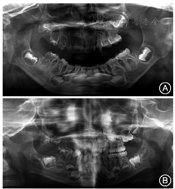

病例2:患者女性,7岁,因"右上颌恒牙未萌出"于2019年1月就诊于四川大学华西口腔医院口腔外科。患者4年多前曾出现过龋齿(具体牙位不详)、面部肿胀等情况,余无明显异常。口内检查见11、12、16、46未萌出,26出龈,36萌出;51、54缺失;52、53、55残冠,Ⅰ度松动,有叩痛,牙龈红肿;口腔卫生尚可。

曲面体层X线片显示,可见11—16恒牙胚,11—16、55密度较对侧牙低,髓腔宽大,硬组织发育不足,牙釉质与牙本质界限不清楚,牙根较短,根尖孔敞开,呈"鬼影样"表现(图2)。诊断:52、53、55残冠,11—16矿化不良。儿童口腔科会诊后制定临床治疗方案为拔除52、53、55残冠后行间隙维持。